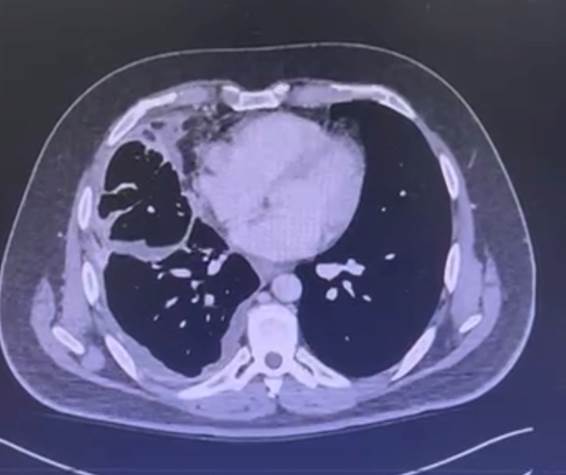

Entre fevereiro e março de 2024, por conta da interrupção no fornecimento do medicamento, o paciente permaneceu 30 dias sem tratamento e evoluiu com dispneia importante, necessitando internação hospitalar e oxigenoterapia. Houve elevação de 250% do CEA para 16,6 em 27/3/24 e nova tomografia de tórax de 21/4/24 evidenciou importante aumento do volume tumoral, com velamento de todo o hemitórax direito por massa de aspecto heterogêneo, com realce por meio de contraste e áreas hipodensas/liquefeitas em permeio, além de surgimento de linfonodomegalias axilares à direita (Figura 2).

As adenomegalias foram biopsiadas visando excluir a hipótese de doença linfoproliferativa, visto a rapidez do crescimento tumoral e confirmando adenocarcinoma. Após discussão do caso em reunião multidisciplinar, foi deliberado o início de um ciclo de quimioterapia com esquema triplet (carboplatina + docetaxel + pemetrexede), considerando hiperprogressão e crise visceral, e encaminhado o tecido para novo painel genético amplo. Observou-se melhora clínica parcial, o que possibilitou alta hospitalar.

Figura 2. Tomografia de tórax com contraste (21/4/24) evidenciou importante aumento do volume tumoral, com velamento de todo o hemitórax direito por massa de aspecto heterogêneo, com realce ao meio de contraste e áreas hipodensas/liquefeitas em permeio, além de surgimento de linfonodomegalias axilares à direita